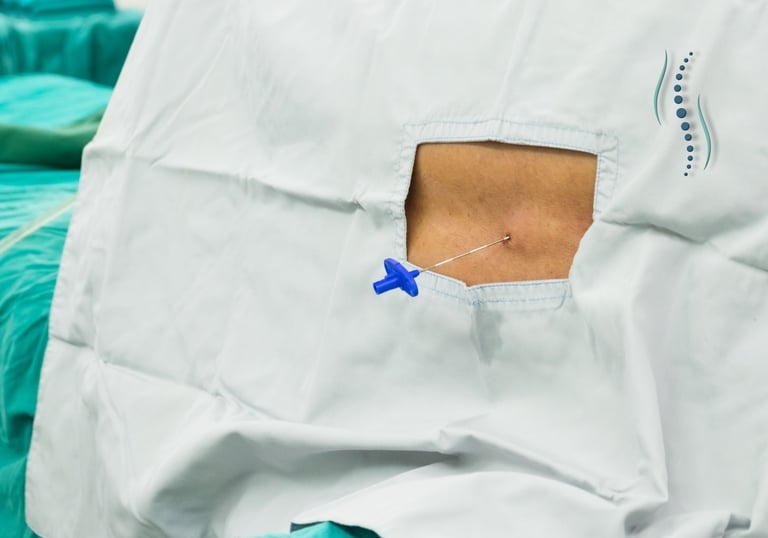

Realiza bloqueos radiculares selectivos y bloqueos facetarios de column a vertebral

Bloqueos guiados por TC